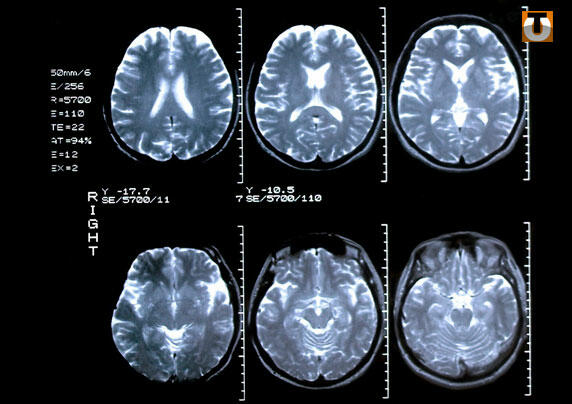

Le 9e congrès de radiologie d’Afrique noire francophone s’est ouvert mercredi à Lomé en présence de nombreux spécialistes venus d’Afrique, de France et bien sûr du Togo. Pendant trois jours, les participants vont débattre sur le thème de l’imagerie médicale au cœur du développement sanitaire en Afrique noire.

Ce congrès qui se tient tous les deux ans accueille également des fabricants et distributeurs d’équipements radiologiques.